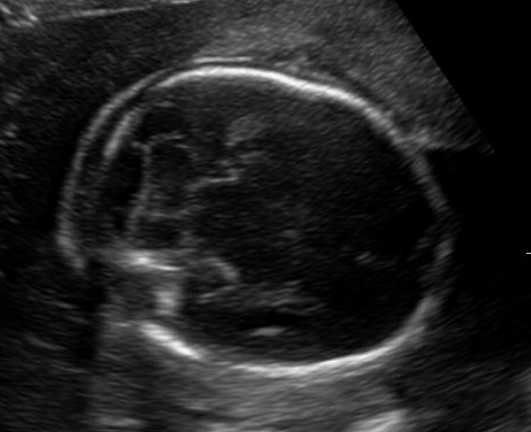

Figure 4.1. Normal cisterna magna and cerebellum. Burn this picture into your mind as what normal looks like. The cisterna magna measures < 10 mm, and the cerebellum maintains a nice normal shape and the central portion of the cerebellum (the vermis) is intact.